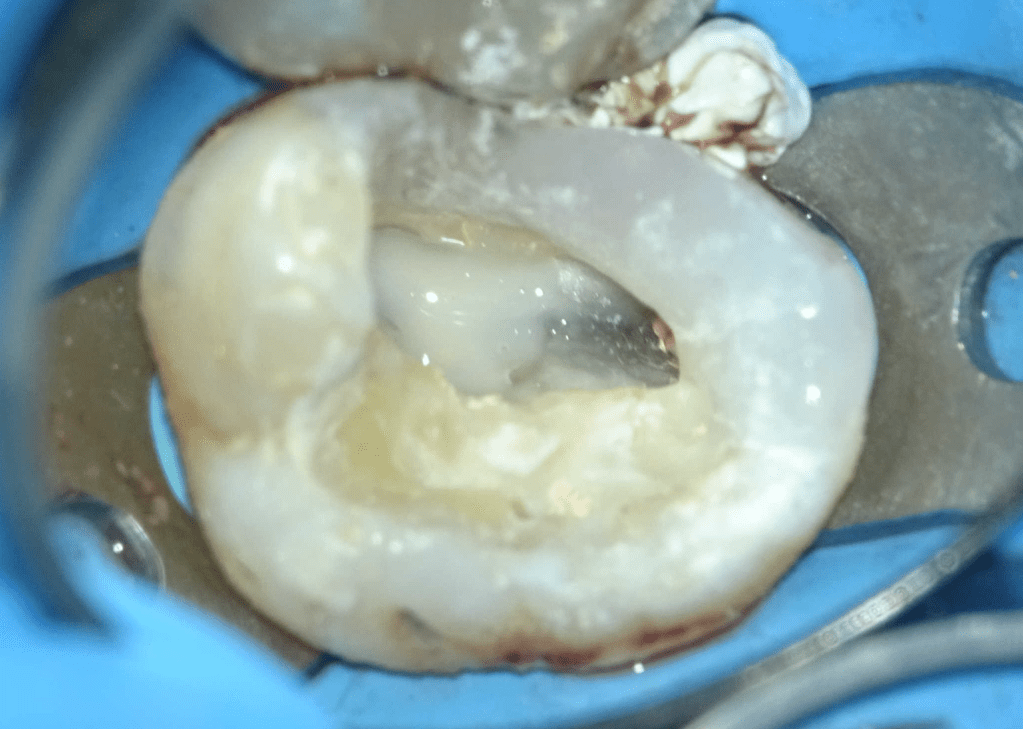

Fisura, remoción amalgama para explorar